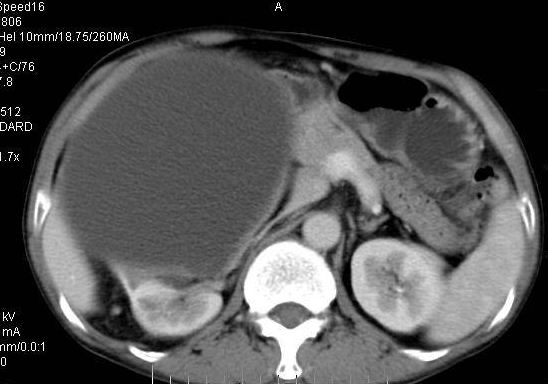

男性 60岁,腹部肿块4年余,肿块逐渐增大,活动性差,无血尿。

ct值测量

右侧多发性肾囊肿,其中之一巨大(不排除其为重复肾积水可能);右肾积水。

右肾脏巨大囊样影、囊壁有钙化,囊样影轻度强化有软组织成份。不除外畸胎瘤可能。

囊性肾癌可能性大,右肾多发囊肿。

右肾上部巨大的囊实性影,实性部分轻度强化。壁有钙化。考虑右肾囊腺癌。右肾盂积水。